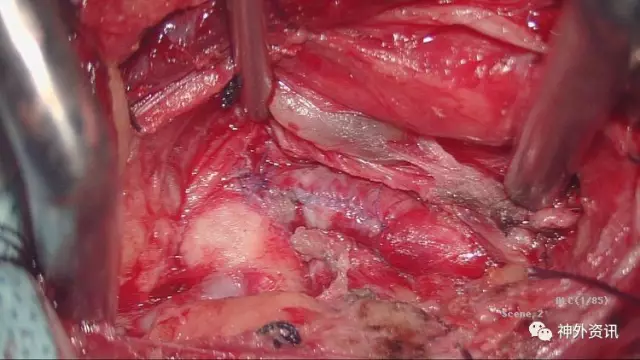

充分游离、显露ⅤA起始段,锁骨下动脉向内外显露各约1.5cm,于血管下留置橡皮条,以方便术中阻断

标记VA内置支架段内膜剥离直切口,阻断锁骨下动脉远近端,马上可以切除支架了

这是剥离支架后的外中膜

显微镜下7-0缝线缝合切口,松开阻断夹,VA管腔充盈好,无活动渗血,手术很顺利